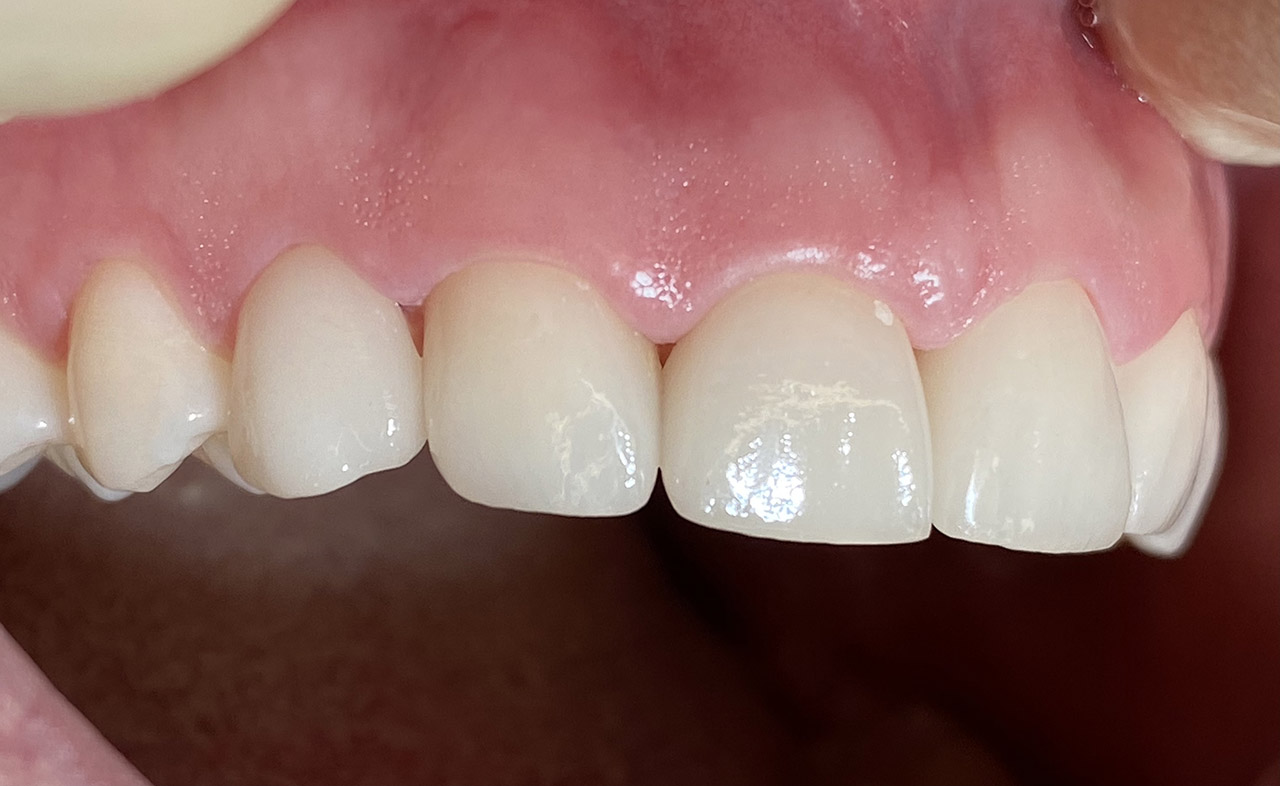

Traumatologie und Endodontie:

Nach Unfall/Sturz mittlerer Schneidezahn auf Gingivaniveau abgebrochen, Pulpa weit eröffnet, beide Nachbarzähne ebenfalls frakturiert.

Erstversorgung: Pulpektomie der Kronenpulpa, MTA, provisorischer Verschluß mit rosa Glasionomerfüllung.

Wiederaufbau der Nachbarzähne mit mitgebrachten (plus 1 Stein) Zahnstücken mit Kunststoff ergänzt und adhäsiv verklebt.

2. Schritt nach Aushärtung von MTA: Entfernung der Kronenpulpa im Bruchstück zur Vermeidung von Verfärbung, Füllung mit Kunststoff.

Adhäsives zementieren des abgebrochenen Zahnstücks.